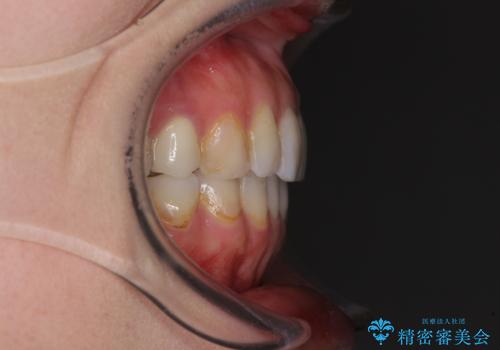

- 失活により変色した歯と不揃いな口元を気にして来院された患者様です。

口元をインビザラインにより歯列を整え、その後に失活している奥歯をオールセラミッククラウンにて補綴治療することとしました。

長時間のマウスピース装着と、患者様自身でのゴムかけに協力いただき、自然な口元に仕上げることができました。

気になっていた変色した歯もオールセラミッククラウンで本物の歯のようになり、患者様には大変満足していただきました。